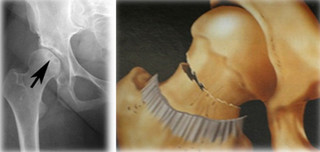

Η νέκρωση της μηριαίας κεφαλής (ΝΜΚ) είναι μια πάθηση του ισχίου, αρκετά συχνή που προσβάλλει και νέους ανθρώπους και η οποία σε τελικό στάδιο καταλήγει σε οστεοαρθρίτιδα του ισχίου.

Νέκρωση μηριαίας κεφαλής